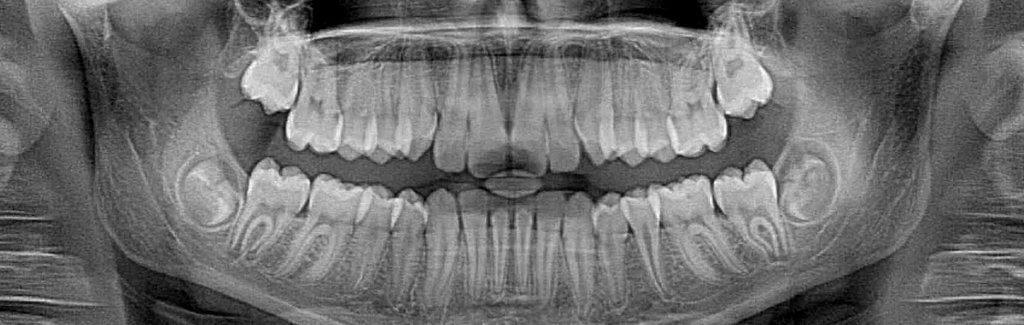

Dental X-rays enable dentists to see decay inside teeth that would not be visible to the naked eye. This allows us to act earlier against cavities, which is much better for the teeth. However, X-rays do expose patients to radiation, which is why you always wear a lead apron when the images are being taken. Thanks to advances in technology, there is now a safer way to take these images.

Film X-rays have been used in dentistry for decades. In the past few years, many forward-thinking dentists like Dr. Cabanban have invested in digital X-ray technology. Film X-rays cost a bit less than digital X-rays but the increased exposure to film X-rays is more harmful to a patient’s overall health. Our digital X-ray emits as much as 85 percent less radiation than traditional X-ray technology.

Digital X-rays are one of the most important new advances in our office. We are not only able to reduce your exposure to radiation but also increase the diagnostic proficiency. In addition to increased diagnostics, we reduce the amount of harmful chemicals and other waste materials associated with traditional X-ray technology. The reduction in waste was a big consideration when deciding to invest in digital technology. We pride ourselves in being environmentally responsible.